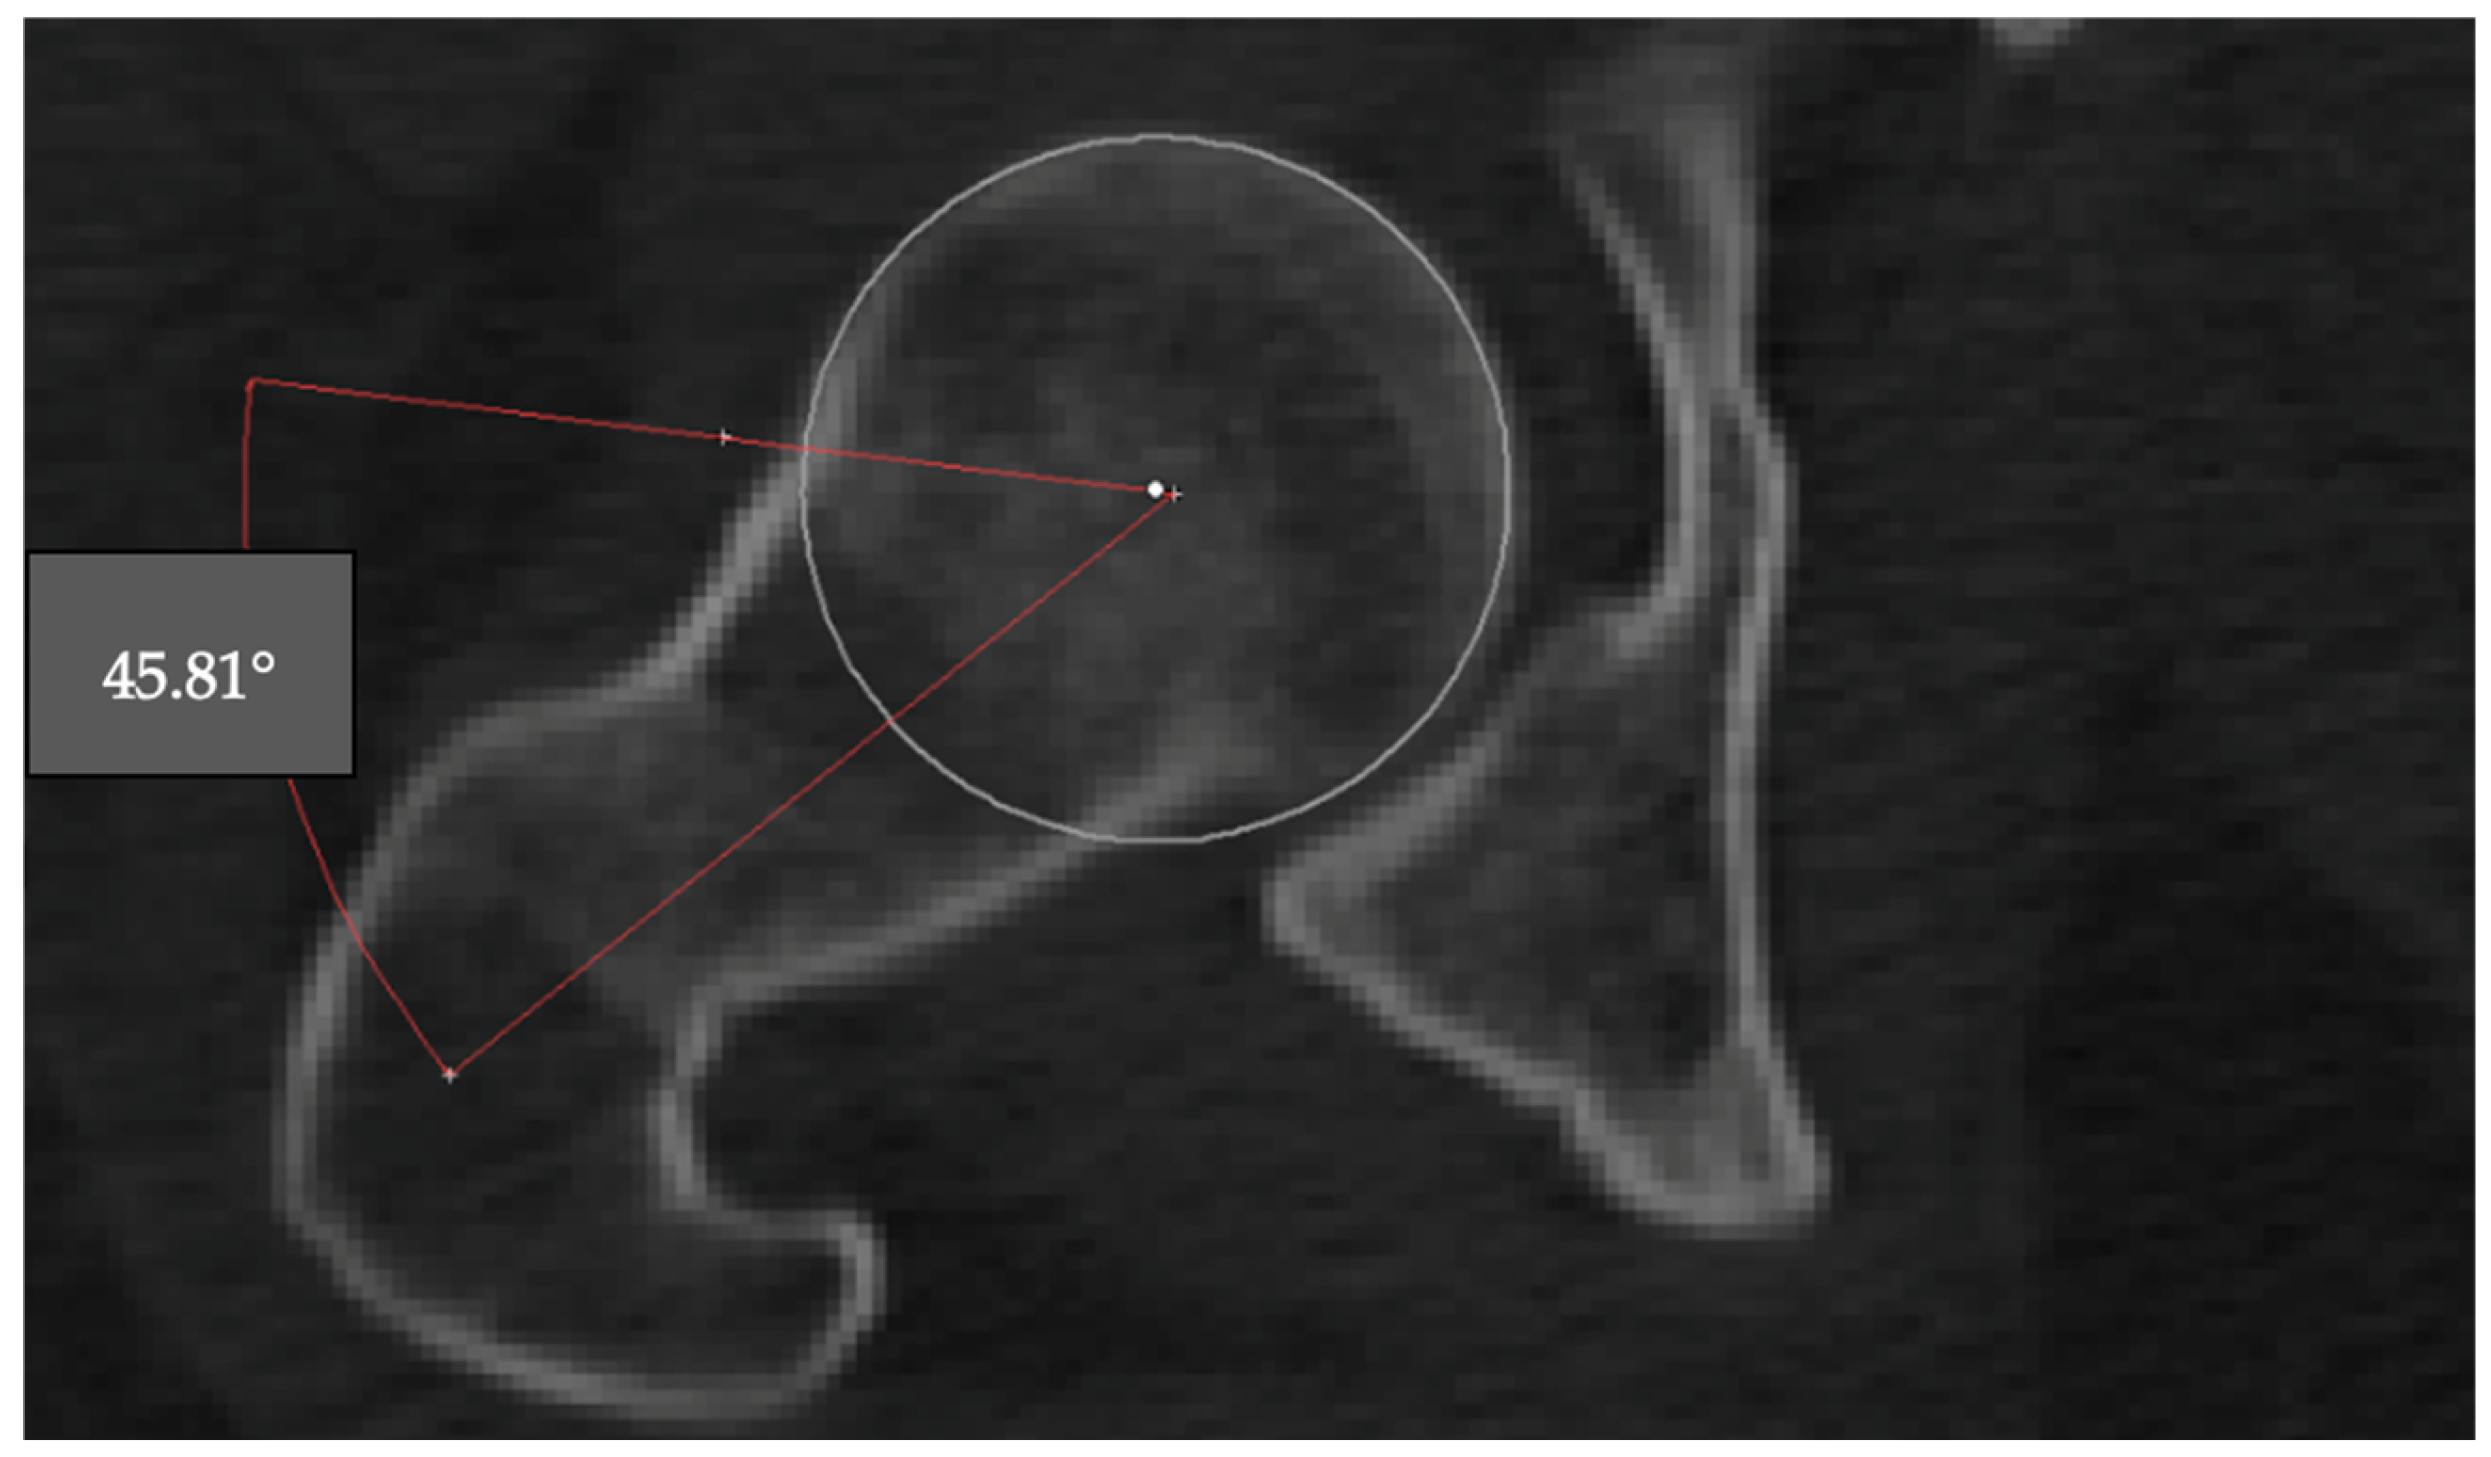

The alpha angle is used to assess the sphericity of the femoral head and detect cam-type deformities. The angle was measured on the axial CT slice where the femoral head appeared largest. A best-fit circle was drawn around the subchondral bone of the femoral head, and two lines were drawn: one from the center of the femoral head through the neck axis, and another from the center to the point where the femoral head extended beyond the circular contour. The angle between these two lines was recorded as the alpha angle (Figure 2).

Figure 2. Measurement of the alpha angle on an axial CT slice. The angle is formed between the femoral neck axis and a line drawn from the femoral head center to the point where the head contour deviates from the best-fit circle (45.81°).